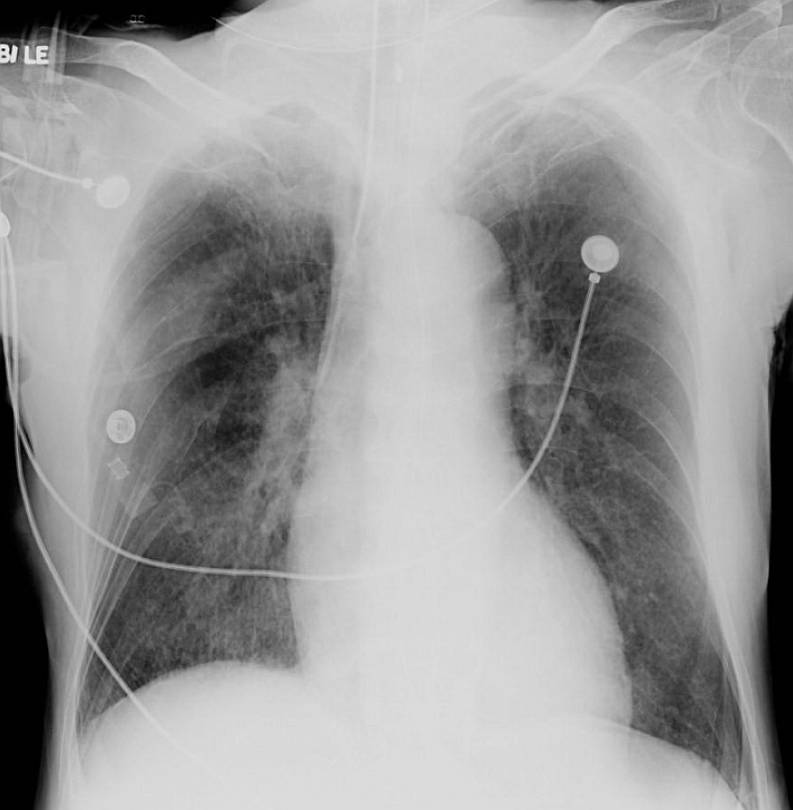

A follow-up chest radiograph obtained 2 days later showed rapid resolution of the previously seen upper zonal opacities (image below).

After stabilization from the neurological point of view, the patient was discharged home. The clinical and radiological findings in this case were consistent with neurogenic pulmonary oedema (NPE).

In the context of traumatic related head injuries, it can be confused with pulmonary contusions. Since cases of NPE might be associated with a mild degree of leukocytosis, NPE can be also mistaken for pneumonia. The major hint to the diagnosis is that NPE develops shortly after the intra-cranial insult and resolves quickly within 1-2 days (2).